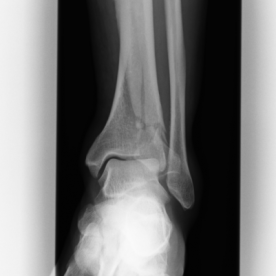

Röntgenbilder